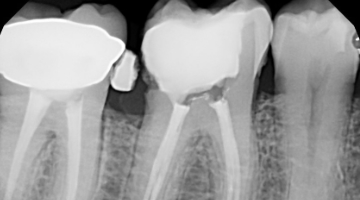

Slide show: Root canal treatment - Mayo Clinic